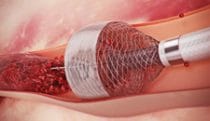

DES that mimics vessel function

Animation -

Clot removal

Work -

Treatment for arteriovenous fistulas

Work -

Stent deployment

Illustration -